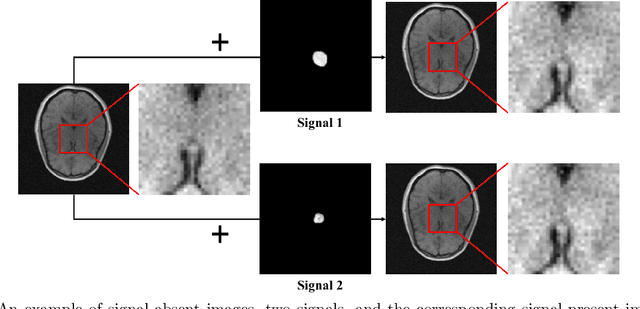

The objective optimization of medical imaging systems requires full characterization of all sources of randomness in the measured data, which includes the variability within the ensemble of objects to-be-imaged. This can be accomplished by establishing a stochastic object model (SOM) that describes the variability in the class of objects to-be-imaged. Generative adversarial networks (GANs) can be potentially useful to establish SOMs because they hold great promise to learn generative models that describe the variability within an ensemble of training data. However, because medical imaging systems record imaging measurements that are noisy and indirect representations of object properties, GANs cannot be directly applied to establish stochastic models of objects to-be-imaged. To address this issue, an augmented GAN architecture named AmbientGAN was developed to establish SOMs from noisy and indirect measurement data. However, because the adversarial training can be unstable, the applicability of the AmbientGAN can be potentially limited. In this work, we propose a novel training strategy---Progressive Growing of AmbientGANs (ProAGAN)---to stabilize the training of AmbientGANs for establishing SOMs from noisy and indirect imaging measurements. An idealized magnetic resonance (MR) imaging system and clinical MR brain images are considered. The proposed methodology is evaluated by comparing signal detection performance computed by use of ProAGAN-generated synthetic images and images that depict the true object properties.